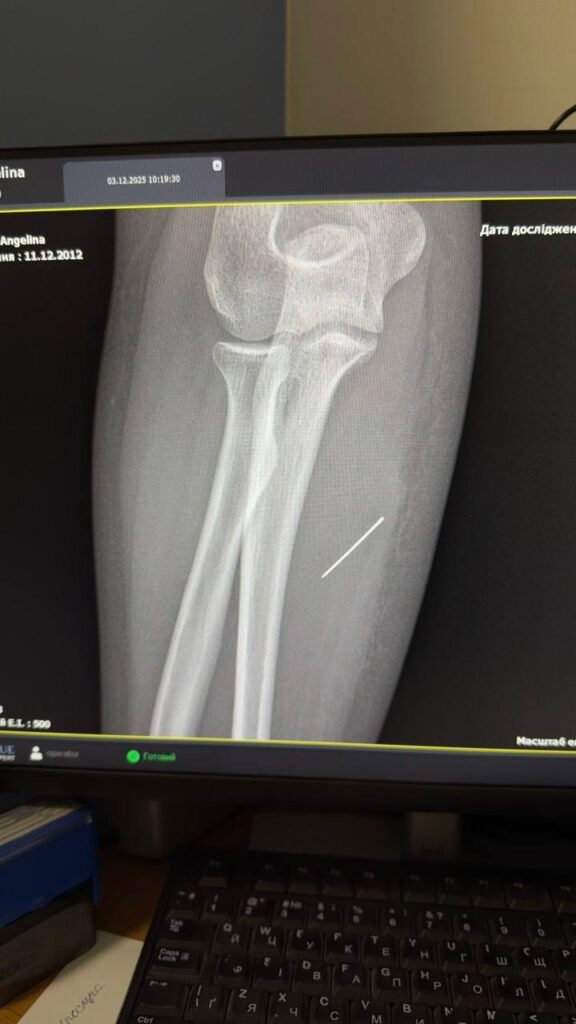

За той тиждень, що Ангеліна проходила з голкою, та просунулася глибше. Вже на рентгені лікарі чітко побачили, що голка зайшла під кутом 45 градусів і застрягла глибоко в товщі м’яза. Якби вона мігрувала ще далі, то могла б пошкодити або судини, або нервові закінчення.

Лікарі розповідають, що під час операції критично важливим було витягнути голку точно за траєкторією її входження, щоб вона не зламалася. Адже пошук дрібних уламків у м’язах є значно важчим завданням. За допомогою рентген-навігації ЕОП хірурги точно визначили місце знаходження стороннього тіла і з допомогою невеликого надрізу правильно і безпечно його вилучили.